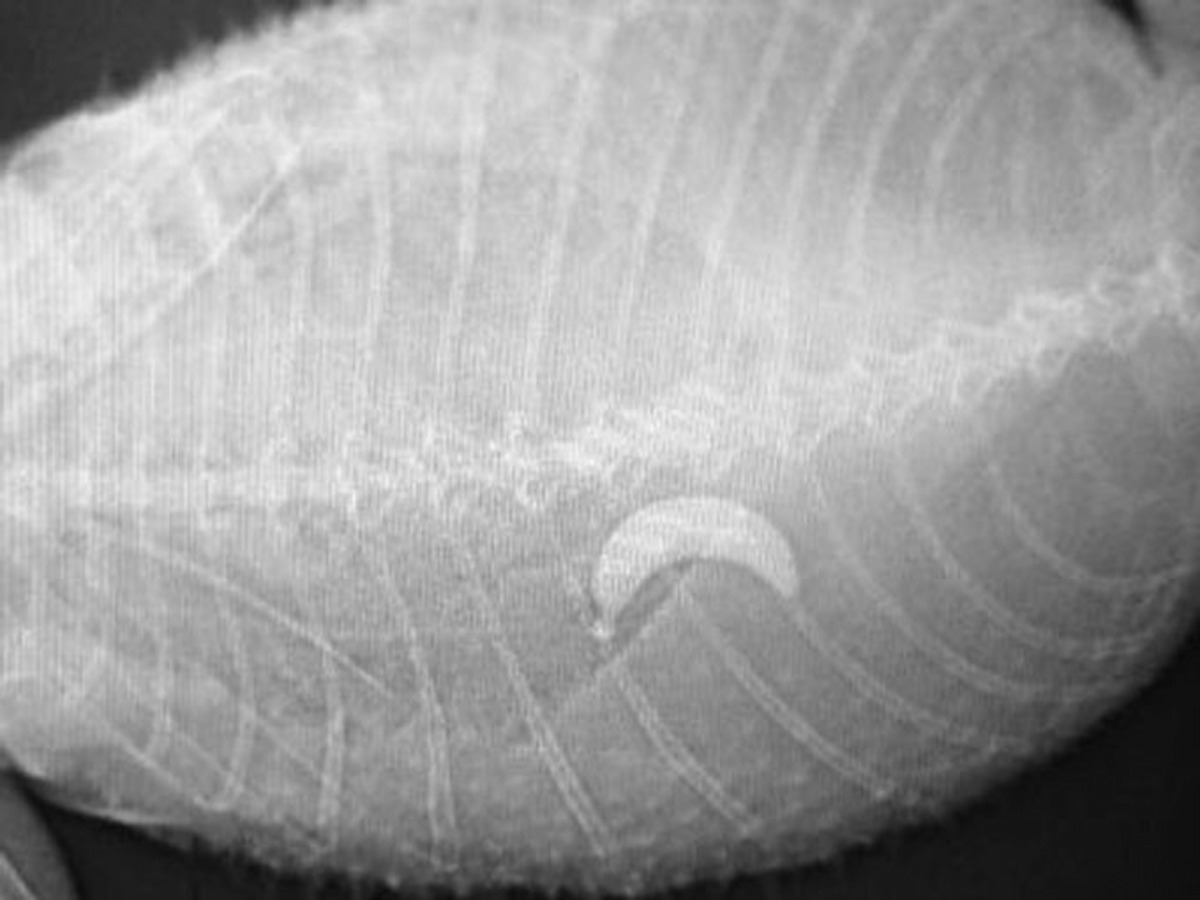

《獸醫執業新聞》早前就舉辦了一年一度的「牠們吃了甚麼?!」比賽,鼓勵獸醫主動上載曾醫治動物的X光片,看看哪隻動物吞下的東西最令人目瞪口呆。呈上的作品亦沒有令大會失望,「食物」種類可謂千奇百趣,錢幣、燈泡,麵包刀、甚至「不求人」皆榜上有名,現在就讓我們一起看看這些寵物的「創舉」吧!